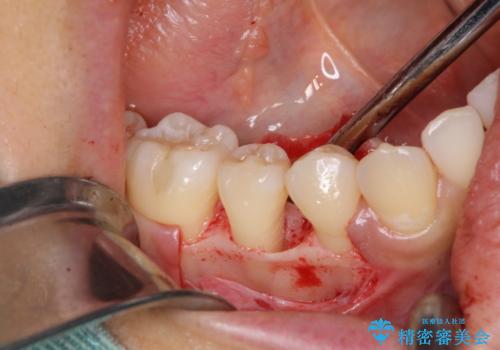

患者様は、他院で右下の歯を抜歯かもと言われました。全体の歯周病はなく、右下の1歯だけ骨が極端に減少していました(初診時歯周ポケット7mm。通常は3mm以下。)。その歯だけ咬合が強いことが原因と考えられたため、咬合を弱くする処置と減少した骨を再生する処置が必要になりました。

骨の再生治療手術をして10か月経過観察をしたのち、骨を平坦化する手術を行い、治療終了となりました。